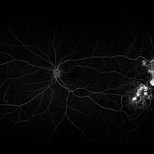

Sickle cell retinopathy (Proliferative) (2 files)

Sickle cell retinopathy (Proliferative) (2 files)

Proliferative sickle retinopathy (1 file)

Proliferative sickle retinopathy (1 file)

Proliferative Sickle Cell Retinopathy (Stage3) (10 files)

Proliferative Sickle Cell Retinopathy (Stage3) (10 files)

Sickle Cell Retinopathy (11 files)

Sickle Cell Retinopathy (11 files)